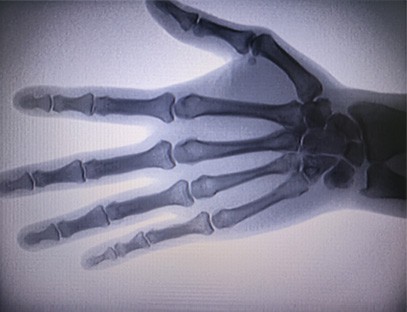

As-c200 nešiojamas rentgeno aparatas yra nešiojamas prietaisas su maža radiacijos doze ir labai saugus. Jis ypač tinka padaliniams ir asmenims, kurių biudžetas yra nepakankamas ir kuriems keliami maži reikalavimai nuotraukoms. Naujoji karta aprūpinta 10 colių didelės raiškos dideliu ekranu, kuris turi didesnį perspektyvos diapazoną ir gali pilnai peržvelgti visą delną. Labiausiai tinka medicininei ortopedinei perspektyvai. Jis gali būti prijungtas prie plėvelės spausdintuvo, kad būtų galima spausdinti ortopedines plėveles, taip pat gali būti naudojamas pramoninėje gamyboje ir bandymuose. Nėra tamsaus kambario, tiesioginė perspektyva, momentinis stebėjimas, didelė skiriamoji geba ir aiškus vaizdas.

Mūsų ortopedinis rentgeno aparatas yra aukštos kokybės gaminys, sukurtas specialiai ortopediniam vaizdavimui. Jis gali būti naudojamas diagnozuojant ir planuojant įvairių ortopedinių būklių, įskaitant lūžius, išnirimus, artritą ir kaulų navikus, gydymą. Jame įdiegta pažangi rentgeno technologija, leidžianti gauti aukštos kokybės vaizdus su sumažintu radiacijos poveikiu. Įrenginys turi didelės raiškos vaizdo sistemą ir gali labai aiškiai užfiksuoti bet kokios kaulų struktūros vaizdus.